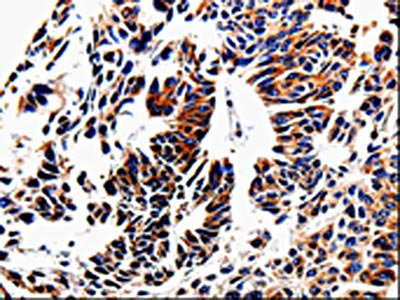

The image on the left is immunohistochemistry of paraffin-embedded Human stomach cancer tissue using CSB-PA732422(ACSBG2 Antibody) at dilution 1/60, on the right is treated with fusion protein. (Original magnification: ×200)

The image on the left is immunohistochemistry of paraffin-embedded Human lung cancer tissue using CSB-PA732422(ACSBG2 Antibody) at dilution 1/60, on the right is treated with fusion protein. (Original magnification: ×200)